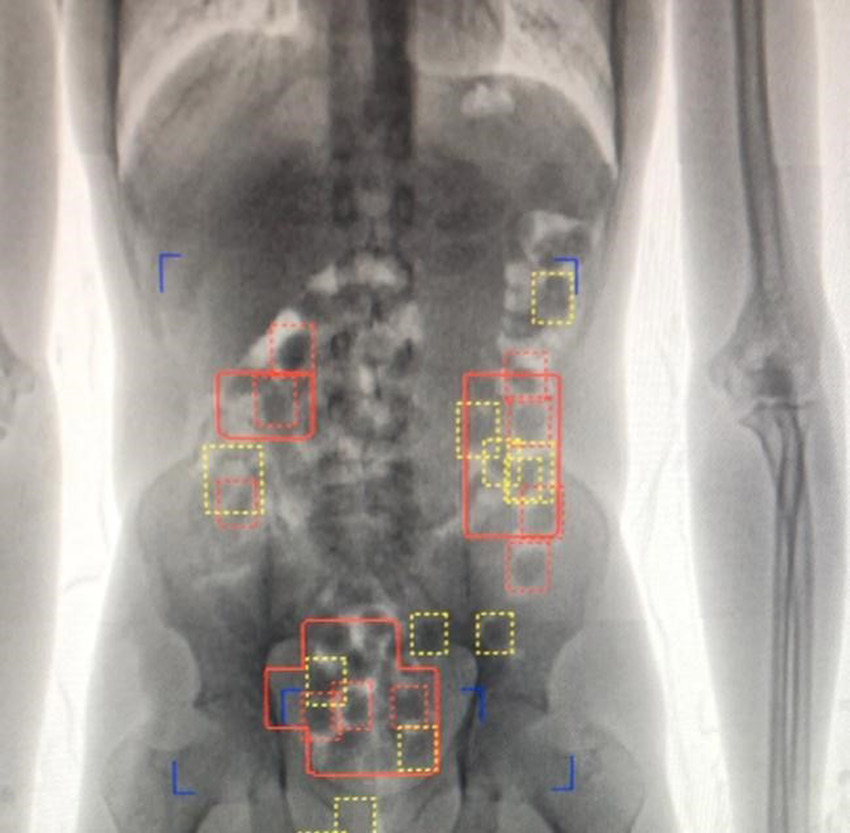

وتعود تفاصيل الواقعة إلى وجود ضابط على واجب عمله في المطار، اشتبه بالمتهم الآسيوي البالغ من العمر 46 عامًا أثناء مروره على نقاط التفتيش، فقام بتحويله إلى المسار الأحمر، وخلال تفتيشه الدقيق باستخدام جهاز الأشعة، تبين وجود أشكال دائرية في أحشائه يعتقد أنها كبسولات تحتوي على مواد مخدرة.

فأحيلت الواقعة الى إدارة مكافحة المخدرات بالمطار، وخلال استكمال الإجراءات طلب المتهم دخول دورة المياه، فتم السماح له بذلك، ليقوم بعدها بإخراج 42 كبسولة صفراء يعتقد احتواؤها على مواد مخدرة من أحشائه، وبعدها بوقت قصير طلب دخول دورة المياه مرة أخرى وأنزل 16 كبسولة إضافية في نوبة ثانية، ثم 28 كبسولة أخرى عند أخذه إلى المستشفى و14 وحدة إضافية في نوبة أخرى.